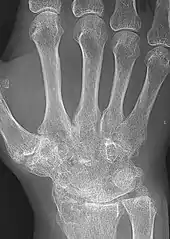

| A hand severely affected by rheumatoid arthritis. This degree of swelling and deformation does not typically occur with current treatment. | |

X-rays of the hands and feet are generally performed when many joints affected. In RA, there may be no changes in the early stages of the disease or the x-ray may show osteopenia near the joint, soft tissue swelling, and a smaller than normal joint space. As the disease advances, there may be bony erosions and subluxation. Other medical imaging techniques such as magnetic resonance imaging (MRI) and ultrasound are also used in RA.[20][68]